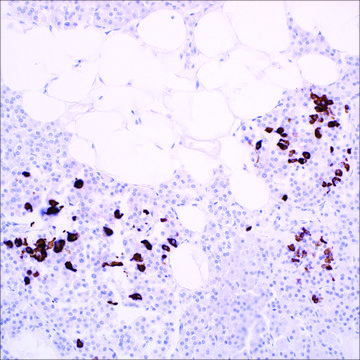

Somatostatin is a peptide hormone widely distributed throughout the body and is an important regulator of endocrine and nervous system function. Somatostatin can also be found in gastrointestinal and bronchopulmonary endocrine cells, thymic endocrine cells, and thyroid C-cells. Anti-somatostatin is a useful marker of D-cells of pancreatic islet cells.1,2 D-cells identification can be used to identify hyperplasia of the pancreatic islets of Langerhans and tumors arising from these cells. Anti-somatostatin recognizes somatostatin-containing cells in pancreatic tumors, islet cell hyperplasia, and islet cells originating in pancreatic ductules.3-7